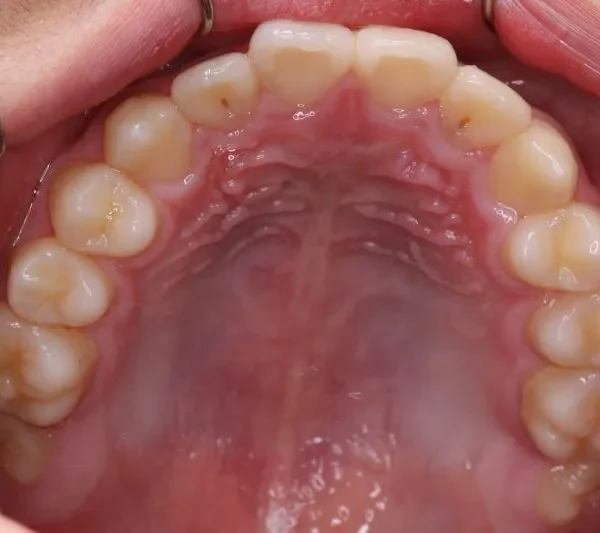

• 初診

初診時年齢 小学校3年生 (男性) 主訴 前歯の噛み合わせが悪い

診断名 切端咬合 装置名

状態 永久歯が生える隙間がない(叢生)

上の歯も下の歯も歯が生えるスペースが少ない為ガタガタしています。

まずは装置で歯のアーチを広げ、歯の生えるスペースを作り、中に入ってる上の前歯を外に押し出して正常な噛み合わせにします。

初診